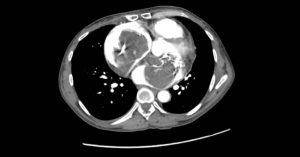

Case Report CTimage